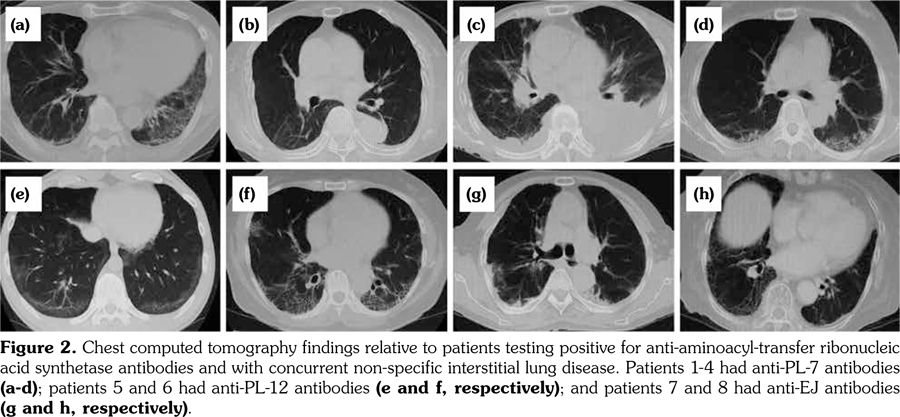

Table 4 contains detailed information (anti-ARS antibody status, age, sex, MTX and bDMARDs treatments, anti-CCP, and RF values) for patients who tested positive for anti-ARS antibody and had also ILD. MTX was administered to one patient while bDMARDs were administered to three patients. Abatacept and etanercept were administered to two and one patients, respectively. Except for one patient who tested positive for anti-PL-7 antibody, anti-CCP antibody and RF titers were high. Chest CT revealed that these patients did not have PM/DM during the clinical course of the disease (Figure 2). Chest CT scans revealed non-specific interstitial pneumonia lung complications in all patients. No characteristic changes were associated with the respective anti-ARS antibodies detected in patient sera. Moreover, patients with rapid progression of lung complications were absent.

Our study revealed the presence of anti-ARS antibodies in sera of 6.1% RA patients in our cohort; 57.1% of anti-ARS antibody-positive RA patients had concomitant ILD. This is a very significant result since, generally, anti-ARS antibodies are detected in PM/DM patients but not in RA patients. Notably, RA patients testing positive for anti-ARS antibodies did not differ from RA patients testing negative for these antibodies in terms of age, sex, RF positivity, and anti-CCP antibody positivity. However, the incidence of ILD complications was significantly higher in RA patients who were positive for anti-ARS antibodies in comparison with patients who tested negative, and CT scan findings from all ILD patients were suggestive of non-specific interstitial pneumonia.